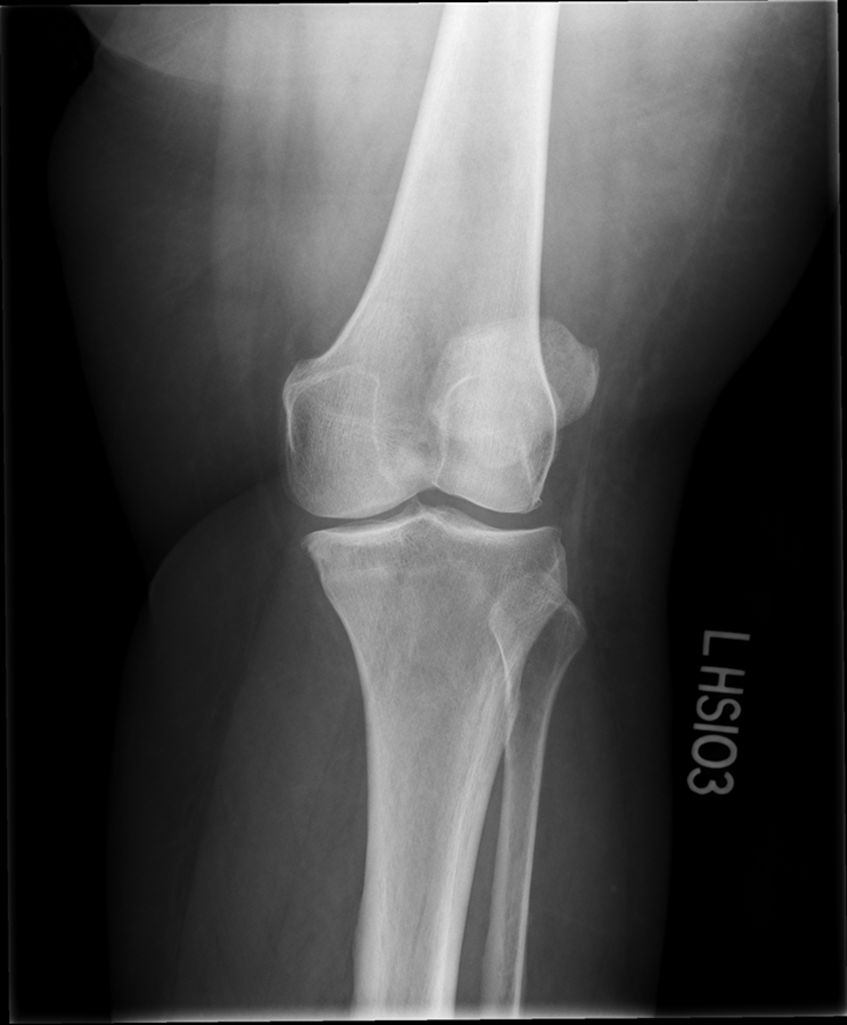

Lateral Rotation, the fibular head is under the tibia, if patella is towards lateral side usually means it is laterally rotated.

Joint space is not open enough

The width of the joint space is not equal

REPEAT FOR LATERAL ROTATION

Not enough superimposition of the fibular head